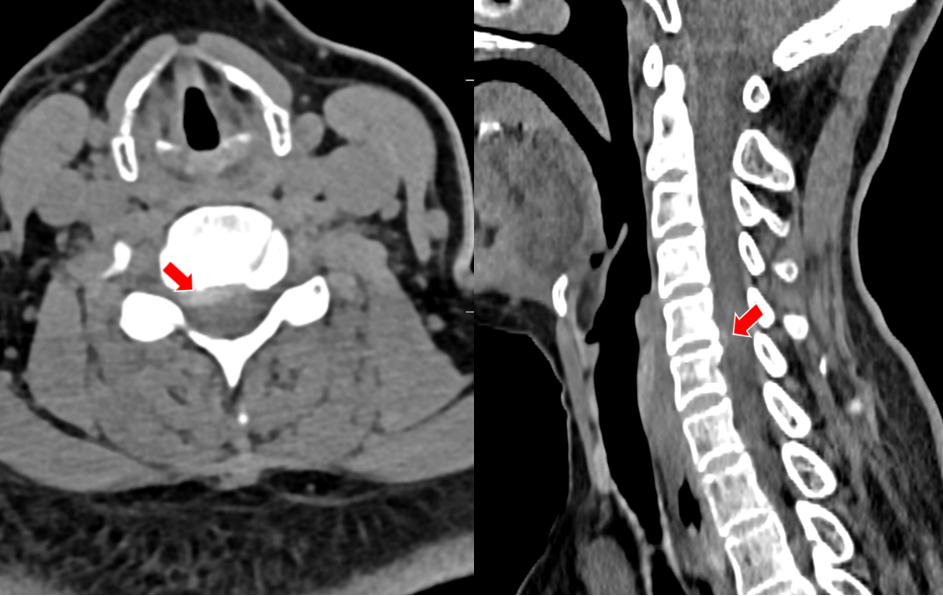

沈阿姨今年58岁,原本正是准备享受生活的年纪,但在今年5月,困扰了她长达4年的颈肩痛明显加重了。短短一周时间,沈阿姨的右上肢就出现了麻木感,吃药、理疗完全无法缓解,症状发展很快,于是立刻来我院骨科就诊。颈椎CT上可以清晰看到,她C4-5的椎间盘明显向右后方突出,椎间隙后缘骨赘增生,导致神经根受压。

(颈椎CT提示患者C5-6的椎间盘突出棒骨性狭窄)

(颈椎CT提示患者C4-5的椎间盘突出(右后方),椎间隙后缘骨赘增生)

在沈阿姨术后第三天,其表姐王阿姨也在她的推荐下来住院了。王阿姨的症状和沈阿姨几乎一样,在住院的前1个月,她右上肢的疼痛感突然加剧,病变的节段是C5-6,看到表妹的手术效果如此显著,她决定也来做手术。